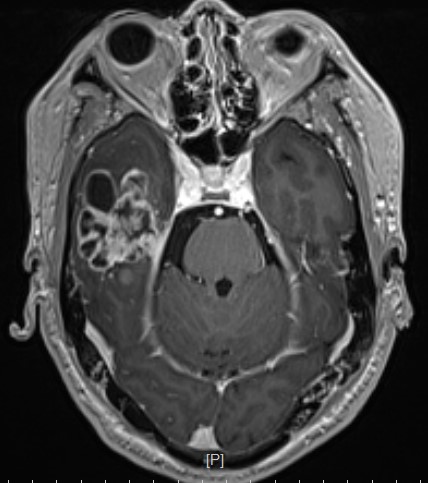

患者,男性,59岁,头痛伴四肢无力一周入院

头部MR提示:右颞叶,岛叶及基底节区巨大占位,胶质母细胞瘤可能性大

冠状位